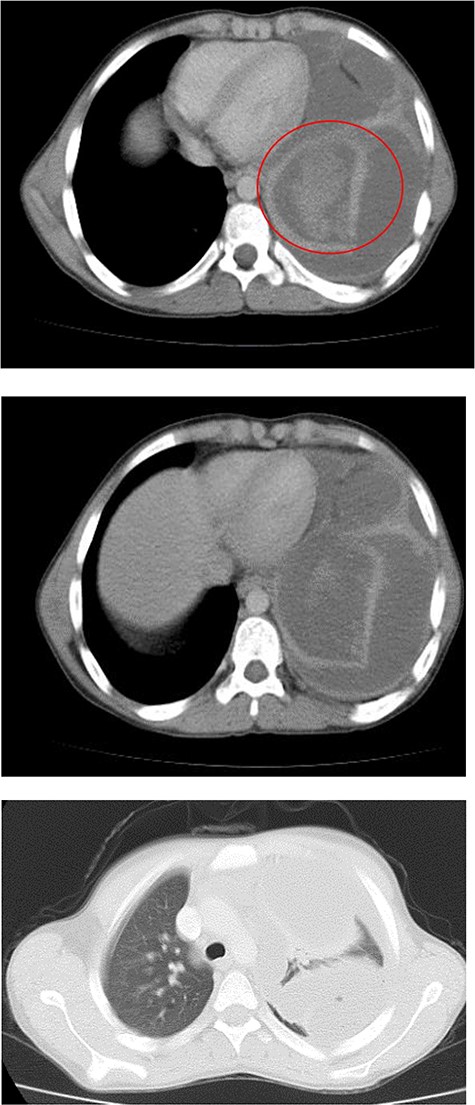

Chest X-ray (Fig. 1) showed an increased density in the left lower zone of the lung. Forty-eight hours later, the patient arrived at the ER along with the computed tomography (CT) scan (Fig. 2). He was in a very poor general condition with pallor, severe dyspnea and clouding of consciousness. Physical examination showed the absence of the left lung sounds, shifted apex beat of the heart to the right and a thready pulse and a blood pressure of about 80/40 mmHg.

A catheter was placed and fluid infusion began, and emergency thoracentesis showed fresh blood. Immediate exploratory thoracotomy was performed (Fig. 3). Three liters of blood were extracted, and the pleural adhesions were liberated. A diaphragmatic hernia was found, with an ischemic strangulated and perforated stomach. The stomach was freed, found vital, its perforation was repaired and it was returned to the abdominal cavity. The opening in the diaphragm was sutured and supported with the omentum. The lung was in good shape.